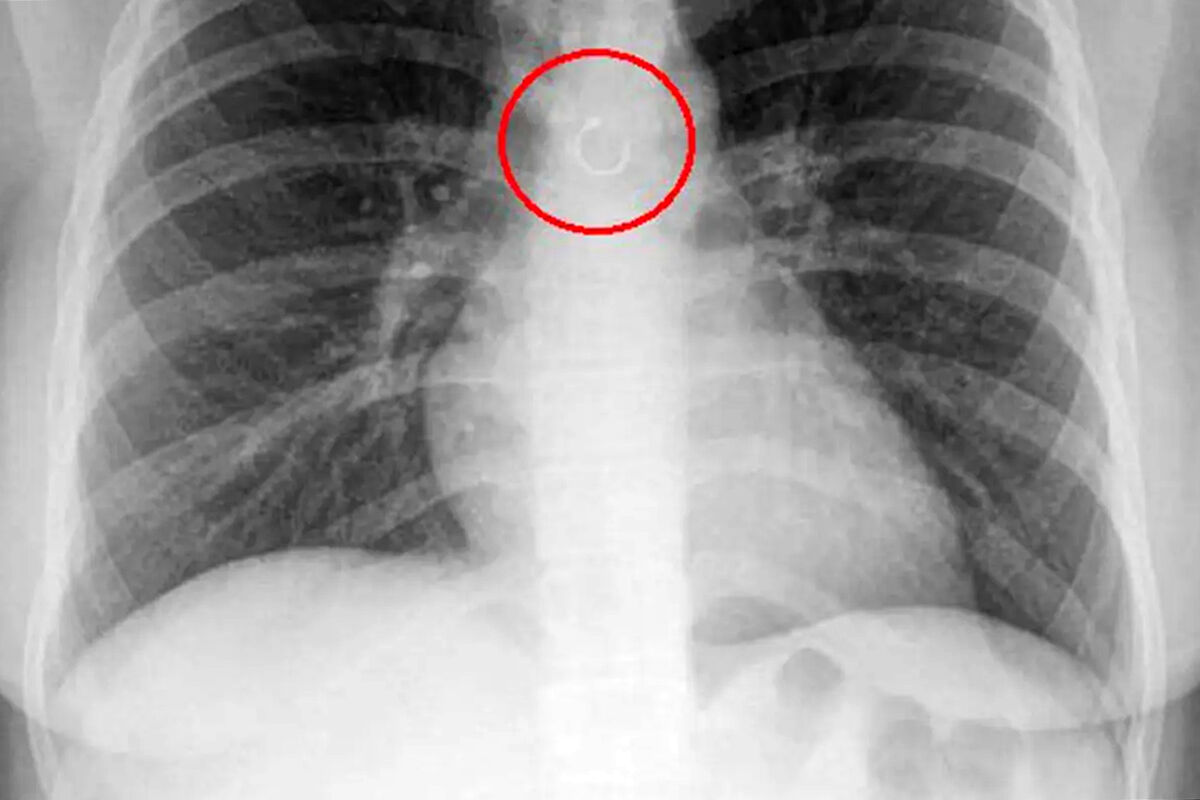

Во время обследования выяснилось, что украшение из пирсинга в носу каким-то образом оказалось глубоко в дыхательных путях девушки и застряло в легких. Металлический элемент находился всего в полумиллиметре от аорты, что могло привести к опасным последствиям, добавили медики.